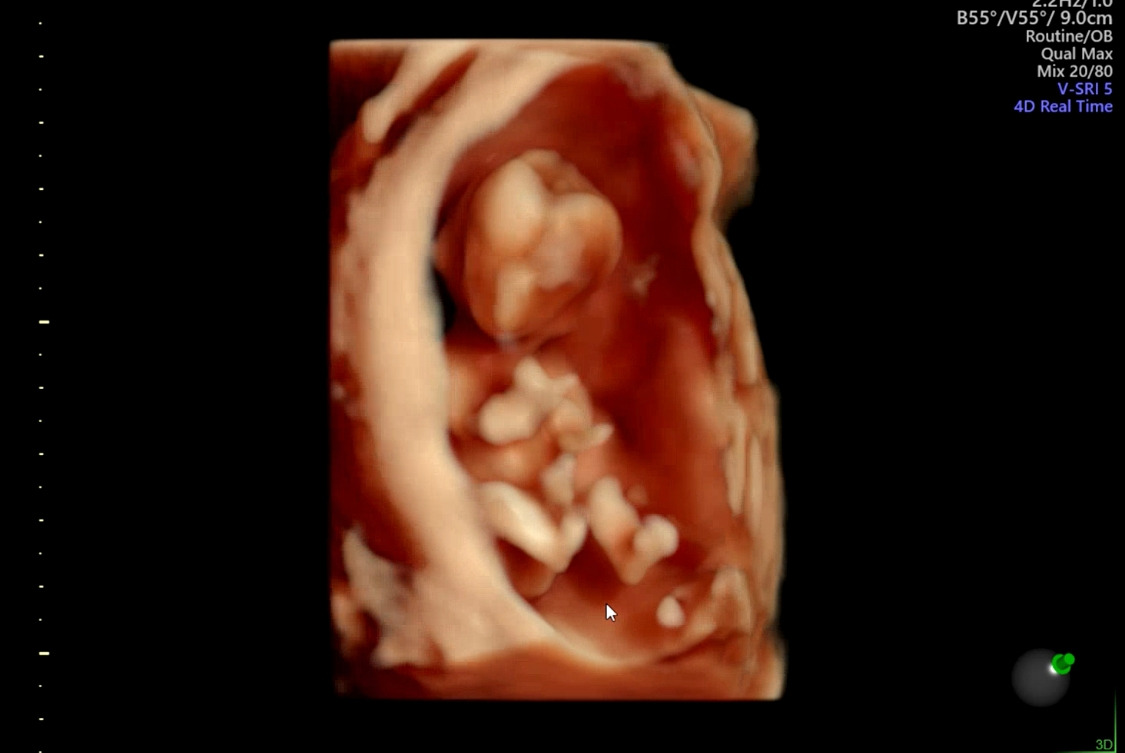

KakaoTalk_20220629_164740923.jpg 노란색 화살표가 가리키는 것이 아기의 심장

확실히 지난 9주에 확인했던 아기보다 많이 컸다. 아기는 건강하게 잘 지내고 있었고, 여전히 역동적인 움직임을 보여줬다. 아기는 잘 있으나, 산모는 잘 있지 못하다. 오늘 있었던 일에 대해 설명하니, 의사 선생님은 흔히 있을 수 있는 증상이라고 하셨다. 또 그러거든 의자에 앉거나 누울 수 있으면 그렇게 휴식을 취하고, 급하게 벌떡 일어나지 말고 몸이 적응할 시간을 주도록 천천히 일어나라고 하셨다. 그리고, 환도서는 증상에 대해서도 초기에 발생할 수 있는 일이고, 딱히 방법은 없다고 하셨다. 오늘은 영양제가 든 수액과, 메스꺼운 속을 조금 진정시켜줄 수 있는 수액을 맞고 돌아가기로.